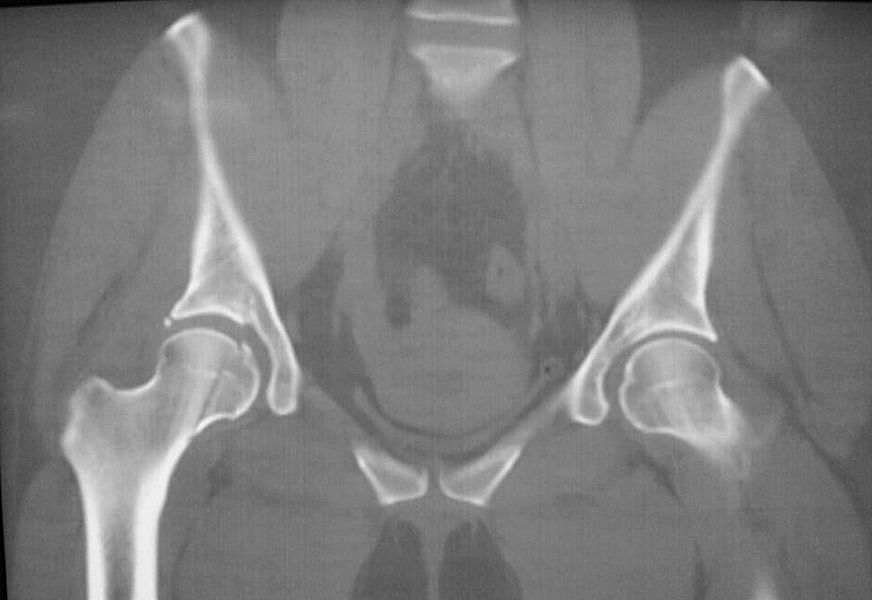

При поступлении выполнено закрытое вправление головки бедра, налажено скелетное вытяжение. Контрольный рентген показал разницу в ширине суставных щелей в сравнении с неповрежденной стороной. Сделали КТ, которое подтвердило наличие внутрисуставного фрагмента задней стенки вертлужной впадины и перелом нижне-медиального сегмента головки со смещением (Pipkin IV).

Через 12 дней выполнен остеосинтез головки 3-мя самокомпрессирующими винтами Герберта. Доступ Kocher-Langenbeck с флип-остеотомией большого вертела и задним хирургическим вывихом головки бедра. Интерпонирующий внутрисуставной фрагмент представлял собой лабрум с тонкой костной пластинкой от заднего края впадины. Фрагмент извлечен и фиксирован техникой spring-plate.